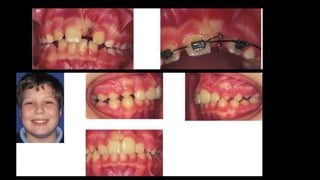

Casos clínicos

4x2